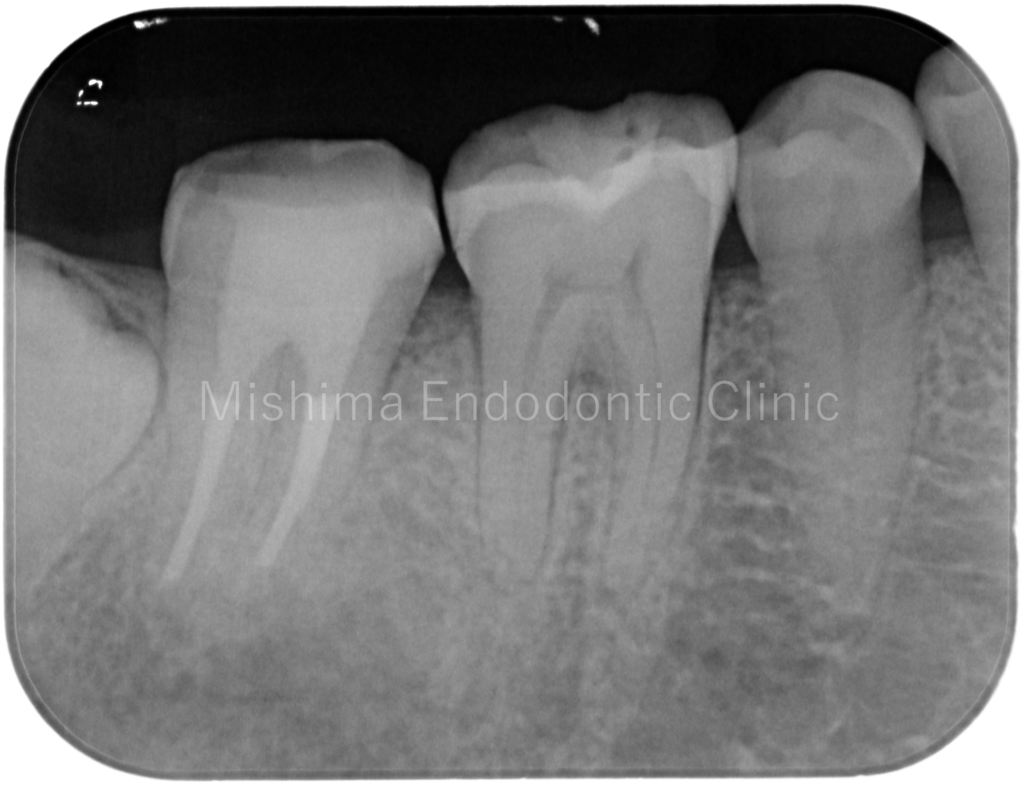

Before

| 主訴 | 根の先に病気があると言われた。 |

| 治療内容 | 既根管治療歯で比較的大きな根尖病変を認めた。根管治療は貼薬無しで即日根管充填。 術後、根尖透過像は消失し経過は良好。 |

術前